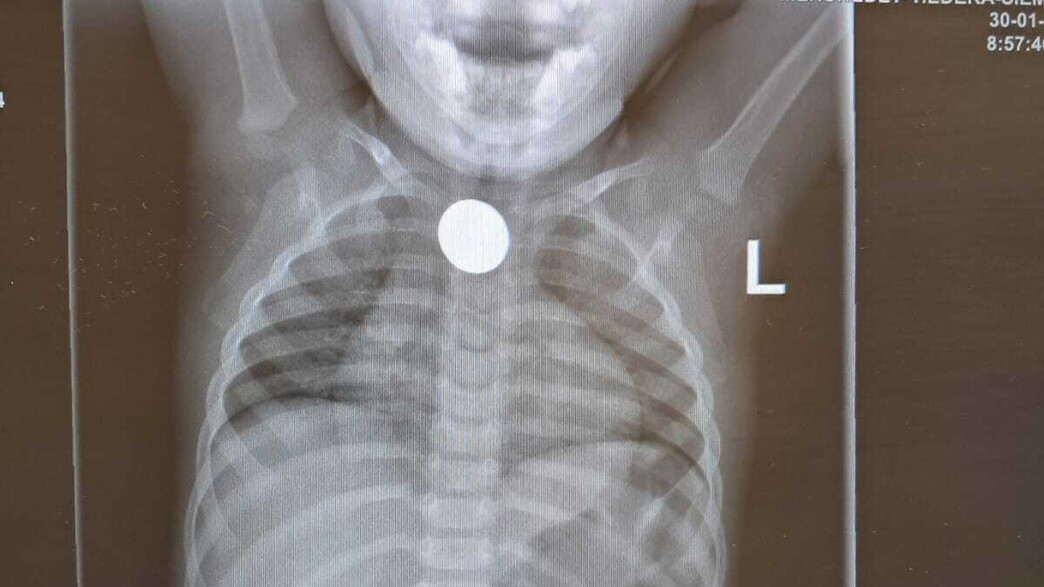

אחד המקרים החמורים היה של ילד בן שש וחצי שהגיע למיון לאחר שבלע חצי שקל בלילה שלפני כן. מאז האירוע הוא סבל מהקאות וכאבי גרון. "הילד הקיא בכל ניסיון לאכול, מה שהעלה את החשד שגוף זר תקוע בוושט", תיאר ד"ר חנא. "מיד ביצענו צילום חזה, שהדגים גוף זר שתקוע בוושט העליון. מדובר במצב שיכול לסכן את החיים, ומצריך הוצאה מיידית של הגוף הזר".

במוקד יצרו מיד קשר עם בית חולים סמוך, לשם הועבר הילד בדחיפות ועבר הוצאה של הגוף הזר - הליך שמוגדר כמציל חיים.